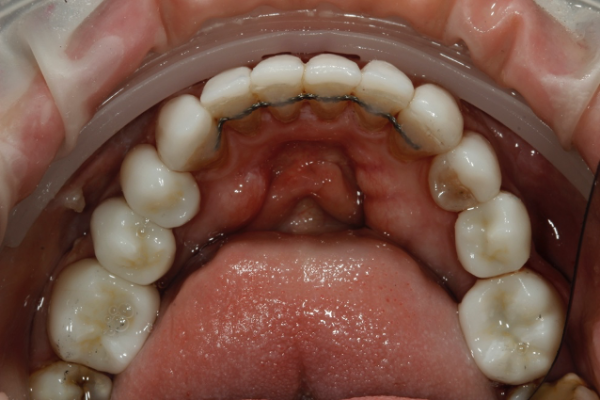

So, prior to a hygiene work up, the patient was then assessed from an orthodontic perspective for short-term pre-restorative orthodontics. This was to improve tooth position (Figures 2 a,b and c) and allow for a less destructive tooth preparation.

The treatment time in fixed orthodontics was 2.5 months. This focused mainly on the maxillary anterior teeth. Dual arch fixed orthodontic appliances were placed. Mainly to allow for use of additional elastics to expedite finishing. Elastics were also used within the upper arch to redistribute space to further minimise invasiveness by reducing the reliance upon IPR (Figure 3).

Post orthodontically, the patient had fixed and removable retainers provided. The patient is educated from the very start that this will be a lifelong commitment for them (Figures 4a and b).

Once the ceramics were fitted in this case, the maxillary upper and lower fixed retainers, which were removed at the stage of preparation, were re-fitted for definitive fixed retention. Thereafter jointly retained with definitive removable Essix retainers (Figures 6 a, b, c and d).